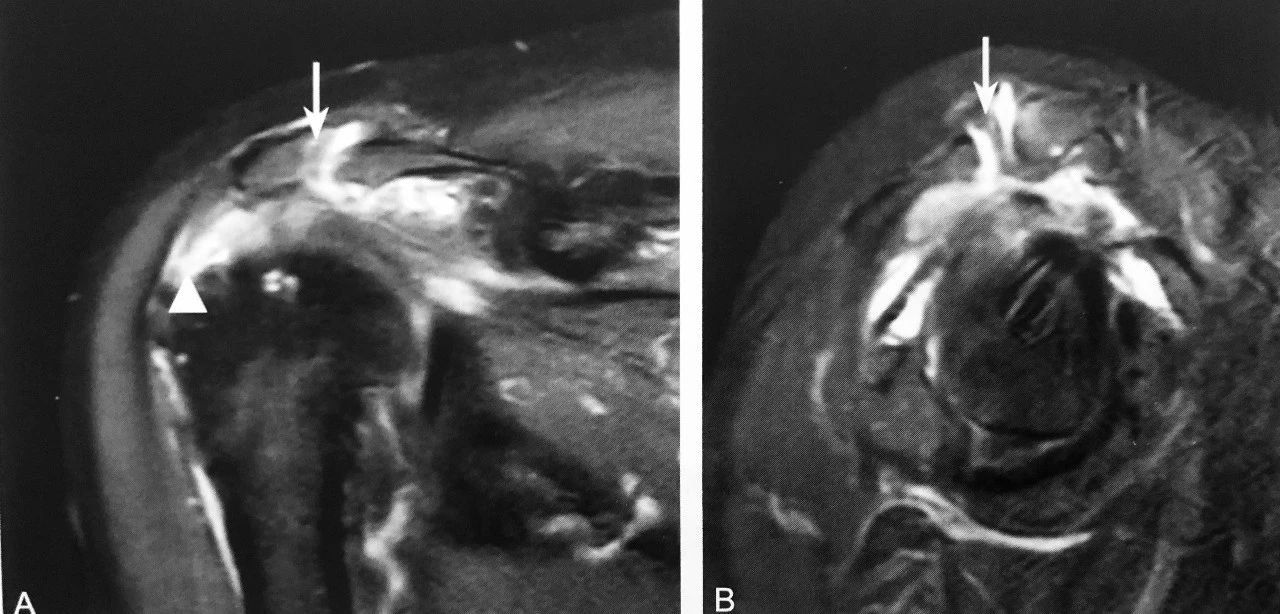

双肩锁关节征:A 图冠状位压脂 PD 序列显示,肩峰关节面下可见游离的条状、未融合肩缝小骨(箭头),肩锁关节囊积液,伴肩峰下-三角肌下滑囊积液,同时可见冈上肌肌腱撕裂(三角);B 图矢状位压脂 PD 序列显示:未融合肩峰小骨与肩峰关节面、肩锁关节形成双肩锁关节,肩锁关节囊积液,伴肩峰下-三角肌下滑囊积液(箭头)

判读要点:

1、在肩关节 MRI 冠状位或矢状位观察;

2、须同一层面同时观察到肩锁关节及肩峰小骨;

3、注意双肩峰关节征与第二肩锁关节区别;

4、观察肩峰小骨是否稳定,如不稳定,是否与邻近软组织产生撞击,此时应注意观察是否伴有周围积液、水肿、肩锁关节损伤及肩袖损伤。